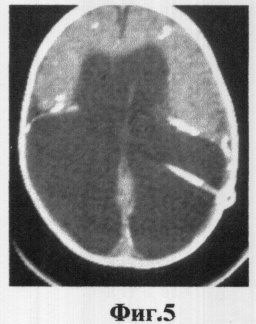

Фиг.5 Демонстрирует грубый порок развития головного мозга, порэнцефалическую гидроцефалию с грубым поражением затылочных долей, однако передние отделы мозга изменены в меньшей степени. Индекс Эванса, измеренный по стандартной методике, равен 0,5, что соответствует легкой степени гидроцефалии. КТ-морфометрические измерения (ЛКИ = 43,5%) демонстрируют гидроцефалию тяжелой степени.